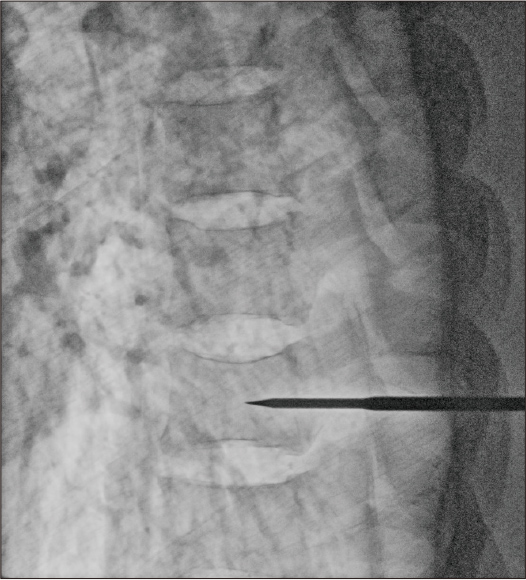

After applying Dynamic processing + noise reduction

Dose: 4.2mA